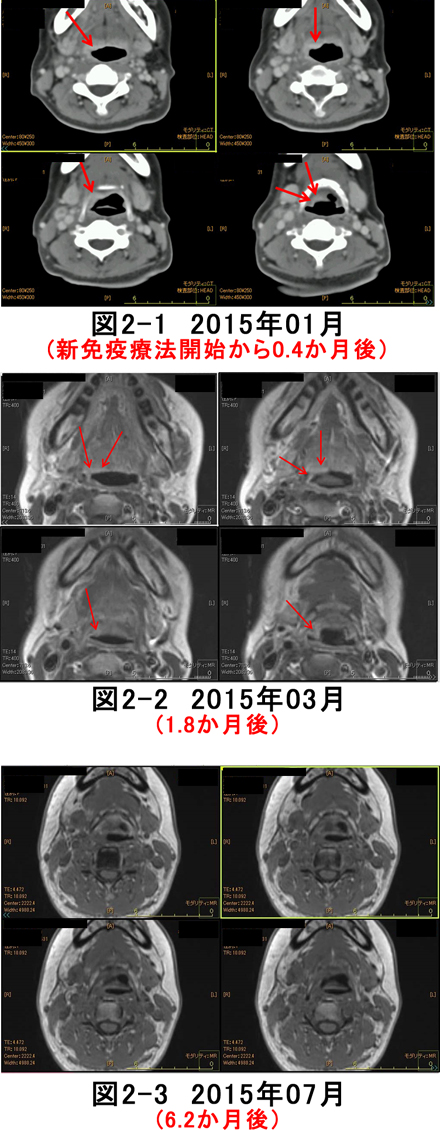

父の癌細胞が消滅したct Mri画像 難病 末期癌からの生還